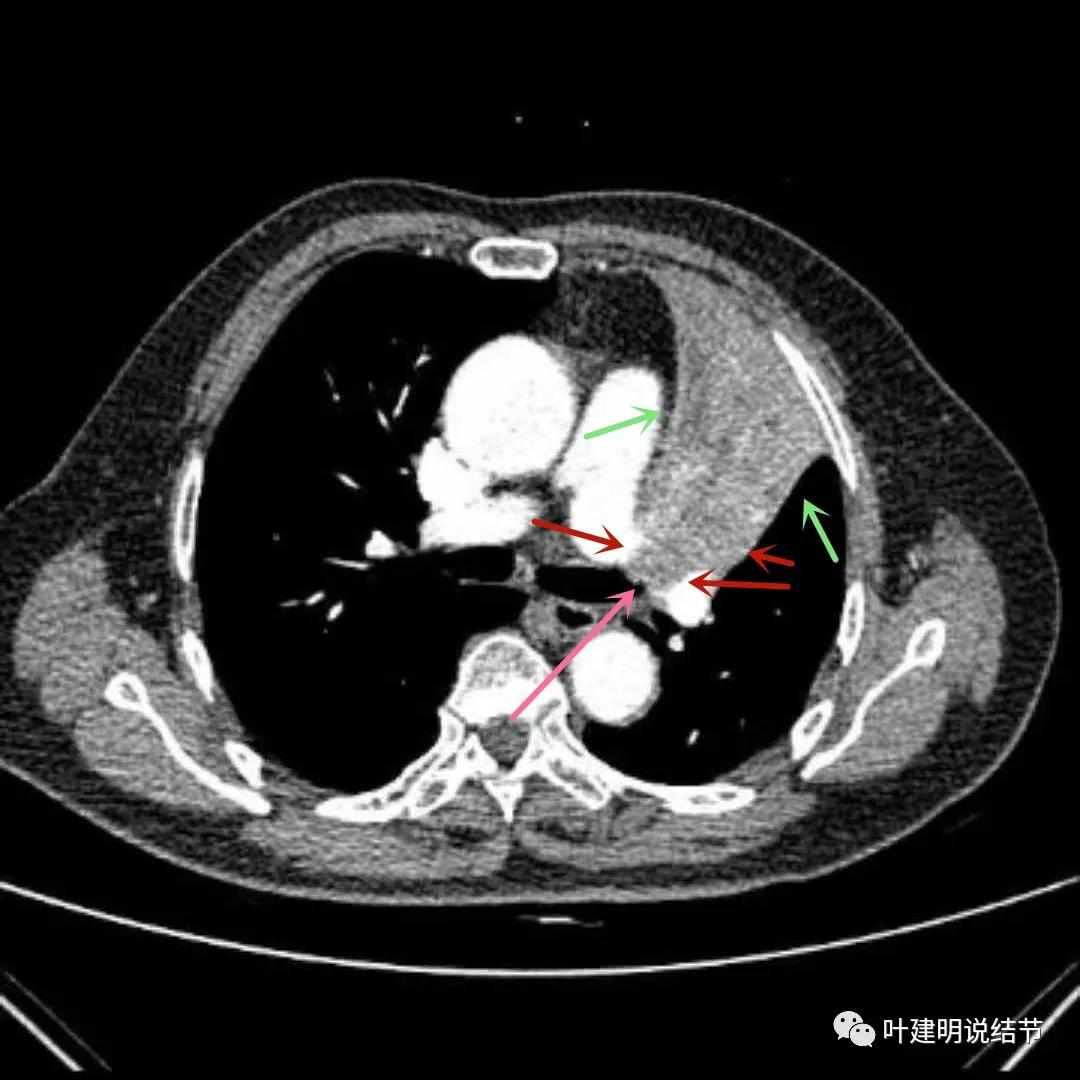

上图绿色箭头所指区域考虑为肺不张,红色示肿瘤处且有不均质与膨胀性,粉色箭头示左上叶开口处已经有肿瘤在,表面不平整。之所以肺动脉中间有软组织影,是因为肿瘤长到肺动脉与支气管之间的缝隙里,相当于血管是跨在肿瘤上,与肿瘤接触的这面是侵犯愈着的。

上图绿色箭头所指区域考虑为肺不张,红色示肿瘤处且有不均质与膨胀性,桔色粗箭头所指处是左侧肺动脉主干,桔色细箭头所示处是叶间动脉干。之所以肺动脉中间有软组织影,是因为肿瘤长到肺动脉与支气管之间的缝隙里,相当于血管是跨在肿瘤上,与肿瘤接触的这面是侵犯愈着的。粉色箭头示肿瘤累及左上叶支气管开口处,表面不平

上图绿色箭头所指区域考虑为肺不张,红色示肿瘤处,桔色箭头所指处分别是左侧肺动脉主干与叶间肺动脉。之所以肺动脉中间有软组织影,是因为肿瘤长到肺动脉与支气管之间的缝隙里。粉色箭头示肿瘤累及左上叶支气管开口处,表面不平;蓝色粗箭头示左下叶支气管开口,细的蓝色箭头示肿瘤与下叶支气管壁的外壁(上下叶开*交口**界处,或称汇总区)关系密切,疑有侵犯的可能